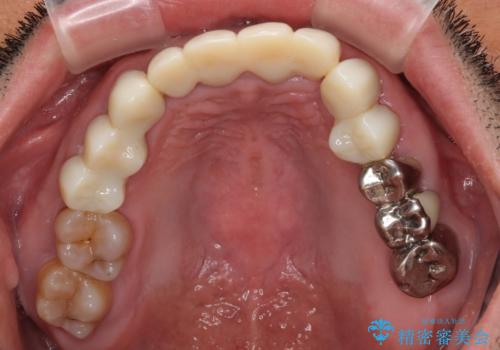

上下ともに前歯のセラミッククラウンによる補綴治療を希望されていましたが、下顎前歯は叢生が強いため、補綴治療前に部分矯正を行って歯列を整えた上で、補綴治療を行うこととしました。

臼歯部には歯周ポケットのある箇所が散見されましたが、まずは前歯を治療したいとのことで、治療を進めました。

ディープバイトにより臼歯部に負担のかかる咬合であったので、補綴治療後には、矯正治療の後戻り防止もかねて、睡眠時にマウスピースを装着するように指示しました。